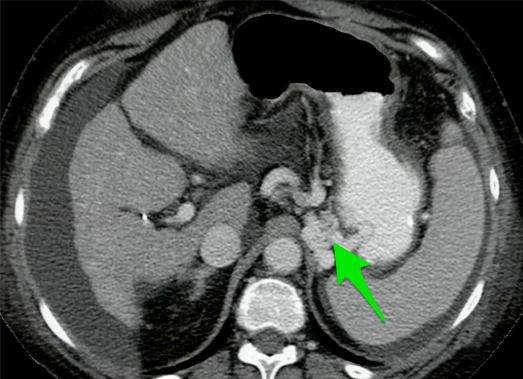

What is your diagnosis in this patient who presented with heart burn?

Sliding hiatal hernia. Note that the mucosal ring is > 2 cm superior to the diaphragm.